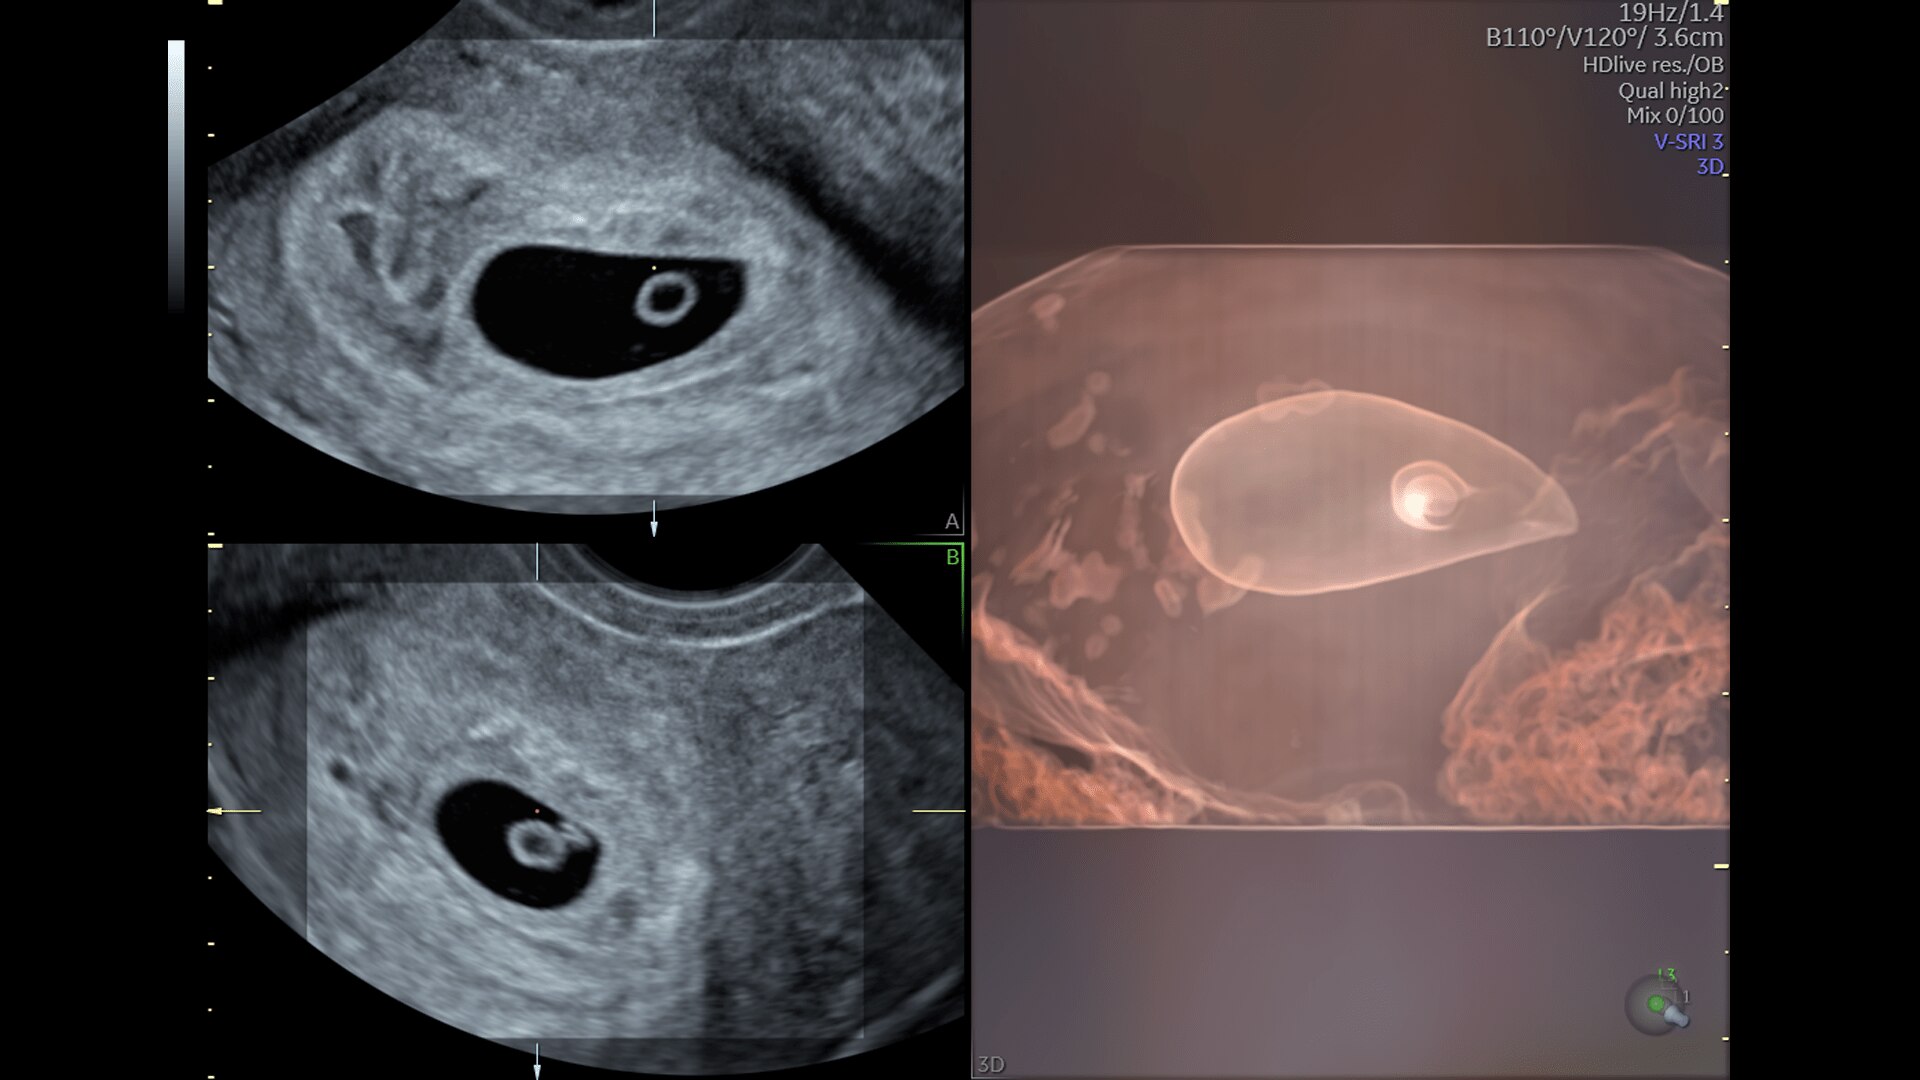

First Trimester Exams

Perform detailed exams with high-resolution for early insights to fetal health